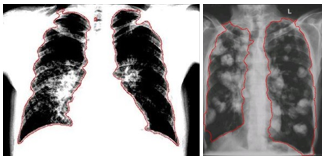

Rysunek 9 Wyniki funkcji konturowej. Sarkoidoza na obraz po lewej stronie, przerzuty nowotworowe na prawej.

Rysunek 11 Sarkoidoza – obraz po lewej stronie, przerzuty nowotworowe – obraz po prawej.

Rysunek 12 Ostateczne wyniki. Szacowana wartość anomalii. Wyniki są widoczne na każdym obrazie, po lewej mamy wyniki sarkoidozy, natomiast po prawej stronie rysunek pokazuje przerzuty nowotworowe.